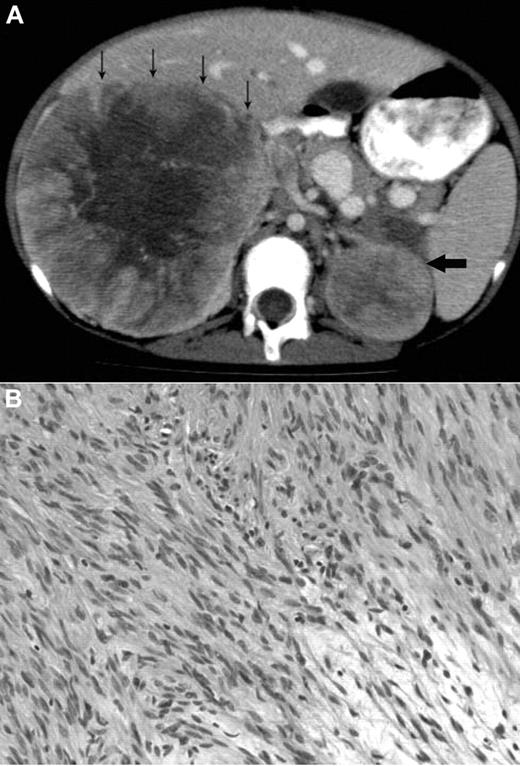

A 12-year-old Metis, Canadian aboriginal group, female presented with a 2-month history of abdominal and back pain with decreased energy. Her medical history included presumed fetal alcohol syndrome with moderate to severe developmental delay, cutis laxa with aortic root dilation, anemia secondary to celiac disease, and seizures. She did not have recurrent or unusual infections. Physical examination at diagnosis showed palpable masses confirmed to be bilateral adrenal masses on abdominal CT scan (Figure 1A). The parents provided written informed consent for the studies in accordance with the Declaration of Helsinki and publication of results per Children's Hospital of Philadelphia Institutional Review Board approval requirements.

Radiologic and histologic findings. (A) Axial CT view of the upper abdomen after intravenous contrast injection and oral contrast administration: Large solid mass in the right suprarenal region with faint central calcification and central stellar hypodensity. Small arrows indicate the anterior border of this mass. The smaller more homogeneous solid lesion in the left suprarenal region is indicated by one large arrow. The right-sided lesion displaces the inferior vena cava anteriorly and medially, and there is visibility of an intracaval defect corresponding to a clot. (B) H&E stain showing elongated spindle cells arranged in a storiform pattern admixed with scattered chronic inflammatory cells (original magnification ×400). The images were captured digitally through a Nikion Eclipse i80 microscope (Nikon) with a 40×/0.75 objective at room temperature without flourochromes. The camera was a Pixelink PL-SW Microscopy (Canimpex Enterprise Ltd) with acquisition software of Pixelink Capture SE Version 4 software for Windows XP (Canimpex Enterprise Ltd). No subsequent image reprocessing occurred.

Complete blood count and differential were normal except for mild and intermittent thrombocytopenia. Serology was positive for EBV-VCA IgG, negative for EBV-VCA IgM, and negative for HIV on more than one occasion. CT revealed right and left adrenal masses 21 × 12 × 11 cm and 6 × 5 × 4.5 cm in size, respectively. Staged tumor mass resections were performed because of initial severe malnutrition related to her celiac disease. The patient has had no recurrence at 26 months after the final resection. Experimental investigations were performed after written consent though an institutional review board–approved protocol at the Children's Hospital of Philadelphia.